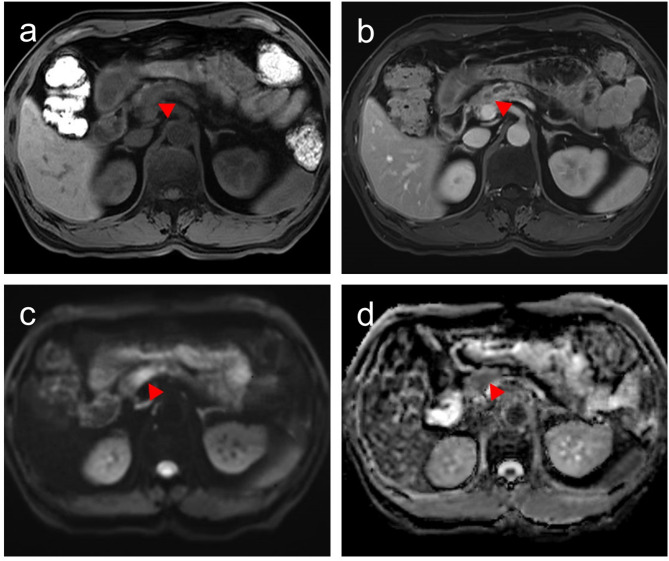

目的:准确预测小胰腺导管腺癌(sPDAC)(≤2 cm)隐匿淋巴结转移(OLNM)对治疗至关重要。本研究旨在探讨sPDAC中与OLNM相关的临床和MRI特征及其病理和预后意义。材料和方法:本回顾性研究纳入了2014年9月至2023年9月间接受手术的135例病理证实的sPDAC患者。分析术前多序列MRI、临床资料及病理特征。采用单因素和多因素logistic回归模型确定sPDAC患者发生OLNM的风险预测因素。采用受试者工作特征(ROC)分析评估诊断表现,采用Kaplan-Meier生存分析评估预后结果。结果:43例(31.9%)sPDAC患者存在OLNM。单因素和多因素分析表明,CA19-9升高(100 U/mL) (OR = 2.404, P = 0.040)和低表观扩散系数(ADC)值(OR = 0.243, P = 0.031)是OLNM的独立预测因子。临床-放射联合模型的AUC为0.740,显著高于CA19-9 (AUC = 0.653, P = 0.021)或ADC单独(AUC = 0.635, P = 0.035)。sPDAC合并OLNM患者淋巴血管浸润率(44.2%,P = 0.013)和病理性脂肪浸润率(86.0%,P = 0.030)较高。OLNM与较差的OS和DFS相关(P = 0.034和0.043)。结论:OLNM具有不良病理特征和较差的预后。术前MRI评估ADC和CA19-9可能有助于识别有OLNM高风险的sPDAC患者。临床试验号:不适用。

Results: OLNM was present in 43 (31.9%) sPDAC patients. Univariate and multivariate analysis identified elevated CA19-9 (> 100 U/mL) (OR = 2.404, P = 0.040) and low apparent diffusion coefficient (ADC) values (OR = 0.243, P = 0.031) as independent predictors of OLNM. The combined clinical-radiological model demonstrated an AUC of 0.740, significantly higher than CA19-9 (AUC = 0.653, P = 0.021) or ADC alone (AUC = 0.635, P = 0.035). sPDAC patients with OLNM exhibited higher rates of lymphovascular invasion (44.2%, P = 0.013) and pathological fat invasion (86.0%, P = 0.030). OLNM was associated with significantly worse OS and DFS (P = 0.034 and 0.043).

Conclusions: OLNM is associated with adverse pathological features and poorer prognosis. The combination of preoperative MRI assessment of ADC and CA19-9 may aid in identifying sPDAC patients at high risk for OLNM.